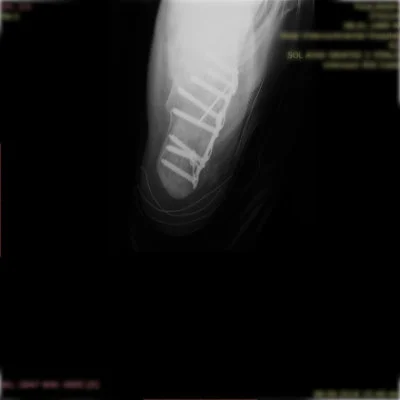

Kas-iskelet sisteminin tüm kırık ve çıkıkları, kas, tendon ve sinir yaralanmaları geniş bir yelpazeyi kapsamaktadır. Her kırık kendi özelinde ayrı ayrı değerlendirilmeli ve her kırık için ameliyat planlaması bu bağlamda yapılmalıdır. Özellikle pelvis-asetabulum kırıkları ortopedik travmada bizler için önemli bir yer tutmaktadır. Bu bölge kırıklarını başarı ile tedavi etmekteyiz.

Özellikle kalça, diz, omurga, kol ve bacak kırıkları gibi durumlarda hızlı ve doğru müdahale, iyileşme sürecini büyük ölçüde etkiler.

Prof. Dr. Halil Burç kliniği olarak, bu tür acil durumlarda sadece yaraları dikmek ya da kırığı sabitlemekle yetinmiyor; hastanın uzun vadeli hareket kabiliyetini, konforunu ve yaşam kalitesini korumayı hedefliyoruz. İleri düzey tekniklerle yapılan ameliyatlar sayesinde, hastalarımızın günlük yaşamlarına en kısa sürede ve en az sakatlıkla dönebilmesi için çalışıyoruz.